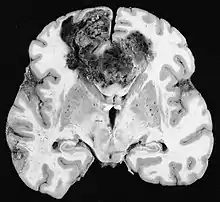

Melanoma

Melanoma is an aggressive skin cancer which has been shown to utilize both angiogenesis and vascular mimicry to drive metastasis and also increase treatment resistance.[1]Metastatic melanoma has very poor survival outcomes with a median survival of 6 months.[19] VM has been identified to be present only in metastatic and very aggressive melanomas. Major biomarkers of VM in melanoma include: VEGF-A, HIF-1A, and Nodal.